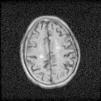

The deficiency of standardized strategies to detect CAA and the bleeding risk that the disease entails, complicate the management of concomitant pathologies with antithrombotic therapy requirement. This is particularly important in patients under hemodialysis, who need anticoagulation treatment during sessions. In regard to antiplatelet treatment, retrospective researches show different outcomes respecting bleeding risk,8 although acetylsalicylic acid is generally avoided and replaced by clopidogrel. Anticoagulation with heparin is also controversial. On the one hand, a case report of CAA-related inflammation treated with enoxaparin 4000IU/12h due to venous thrombosis, described a subsequent big cerebral hematoma which caused death.9 On the other hand, low-molecular-weight heparin (LMWH) is recommended despite cerebral hemorrhage if immobilization extends beyond 3–4 days.10 In the exposed case of the patient, LMWH treatment was kept during hemodialysis sessions, and he continued his previous therapy with clopidogrel. Six days later, a control non-contrast head TC showed the resolution of acute hemorrhage, and due to the remarkable clinical improvement, the patient was discharged from the hospital showing a normal orientation state (Figs. 1 and 2).

Because of its significance for hemodialysis patients, CAA is an important disease in Nephrology sphere. It is already known the importance of controlling parameters like arterial pressure, anemia, or hydroelectrolytic equilibrium in those patients in order to prevent microhemorrhages onset. However, prospective researches should focus on the bleeding risk stratification in CAA patients undergoing hemodialysis, the impact of different antithrombotic treatments in those patients, and emphasize diagnostic methods for CAA, like gradient echo sequences MRI.